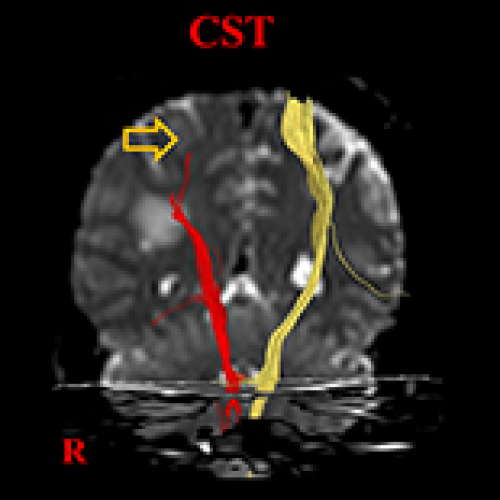

Role of Diffusion Tensor Tractography in Diagnosis of Limb-Kinetic Apraxia in Stroke Patients: A Mini-Narrative Review

DOI: 10.12659/MSM.936417

Med Sci Monit 2022; 28:e936417

18 Apr 2022 : Review article

5,294